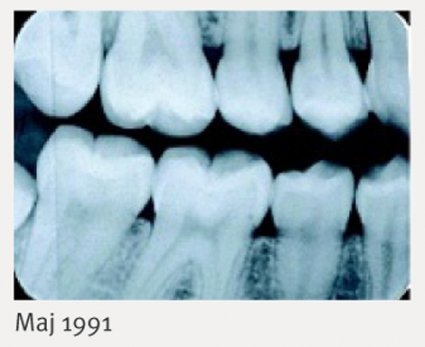

Innan de första mjölktänderna kommer har barnen ofta fula och smärtsamma aftösa sår i munhålan, ibland med nekroser. När tänderna kommer blir inflammationen kronisk och kan utvecklas till tidig tandlossning, ibland redan i förskoleåldern [11]. Vid tidig kronisk gingivit hos barn bör neutropeni eller neutrofilfunktionsdefekt misstänkas.

Innan G-CSF-behandling var tillgänglig drabbades patienterna med Kostmanns syndrom av besvärlig gingivit och tandlossning. Patienter som svarade på G-CSF-behandling med normalisering av ANC förbättrade sitt munstatus. De flesta fortsatte dock att ha problem med parodontit, och en av våra patienter utvecklade svår aggressiv parodontit (Figur 3) [10, 39].

Vid tidigare studier av neutrofilfunktionen hos G-CSF-behandlade patienter har det inte framkommit någon signifikant defekt i själva neutrofilens funktion [40]. När vi tillsammans med kolleger vid Karolinska institutet i Stockholm studerade de antibakteriella peptiderna i neutrofilen hos patienter med Kostmanns syndrom fann vi emellertid mycket låga nivåer av pro-LL-37 och reducerade nivåer av de antibakteriella (alfa)-defensinerna. LL-37 saknades också i saliven [39]. Det förelåg en korrelation mellan avsaknaden av LL-37 och parodontit, och vi bedömde att parodontitproblemen är sekundära till brist på antibakteriella peptider.